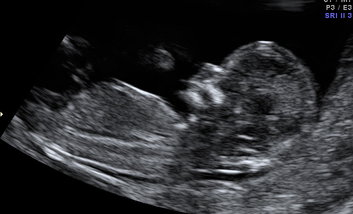

I decided not to find out in scan but now it is really bugging me :) Does this look boy to you?

Thank you for replying, this is my only gender region pic but I was just certain it was the testy's in the middle.

I agree with you...it looks like the scrotum.

That's all I see too and now keep thinking its a boy.

this is the only other pic from my 12+4day scan that may show the nub